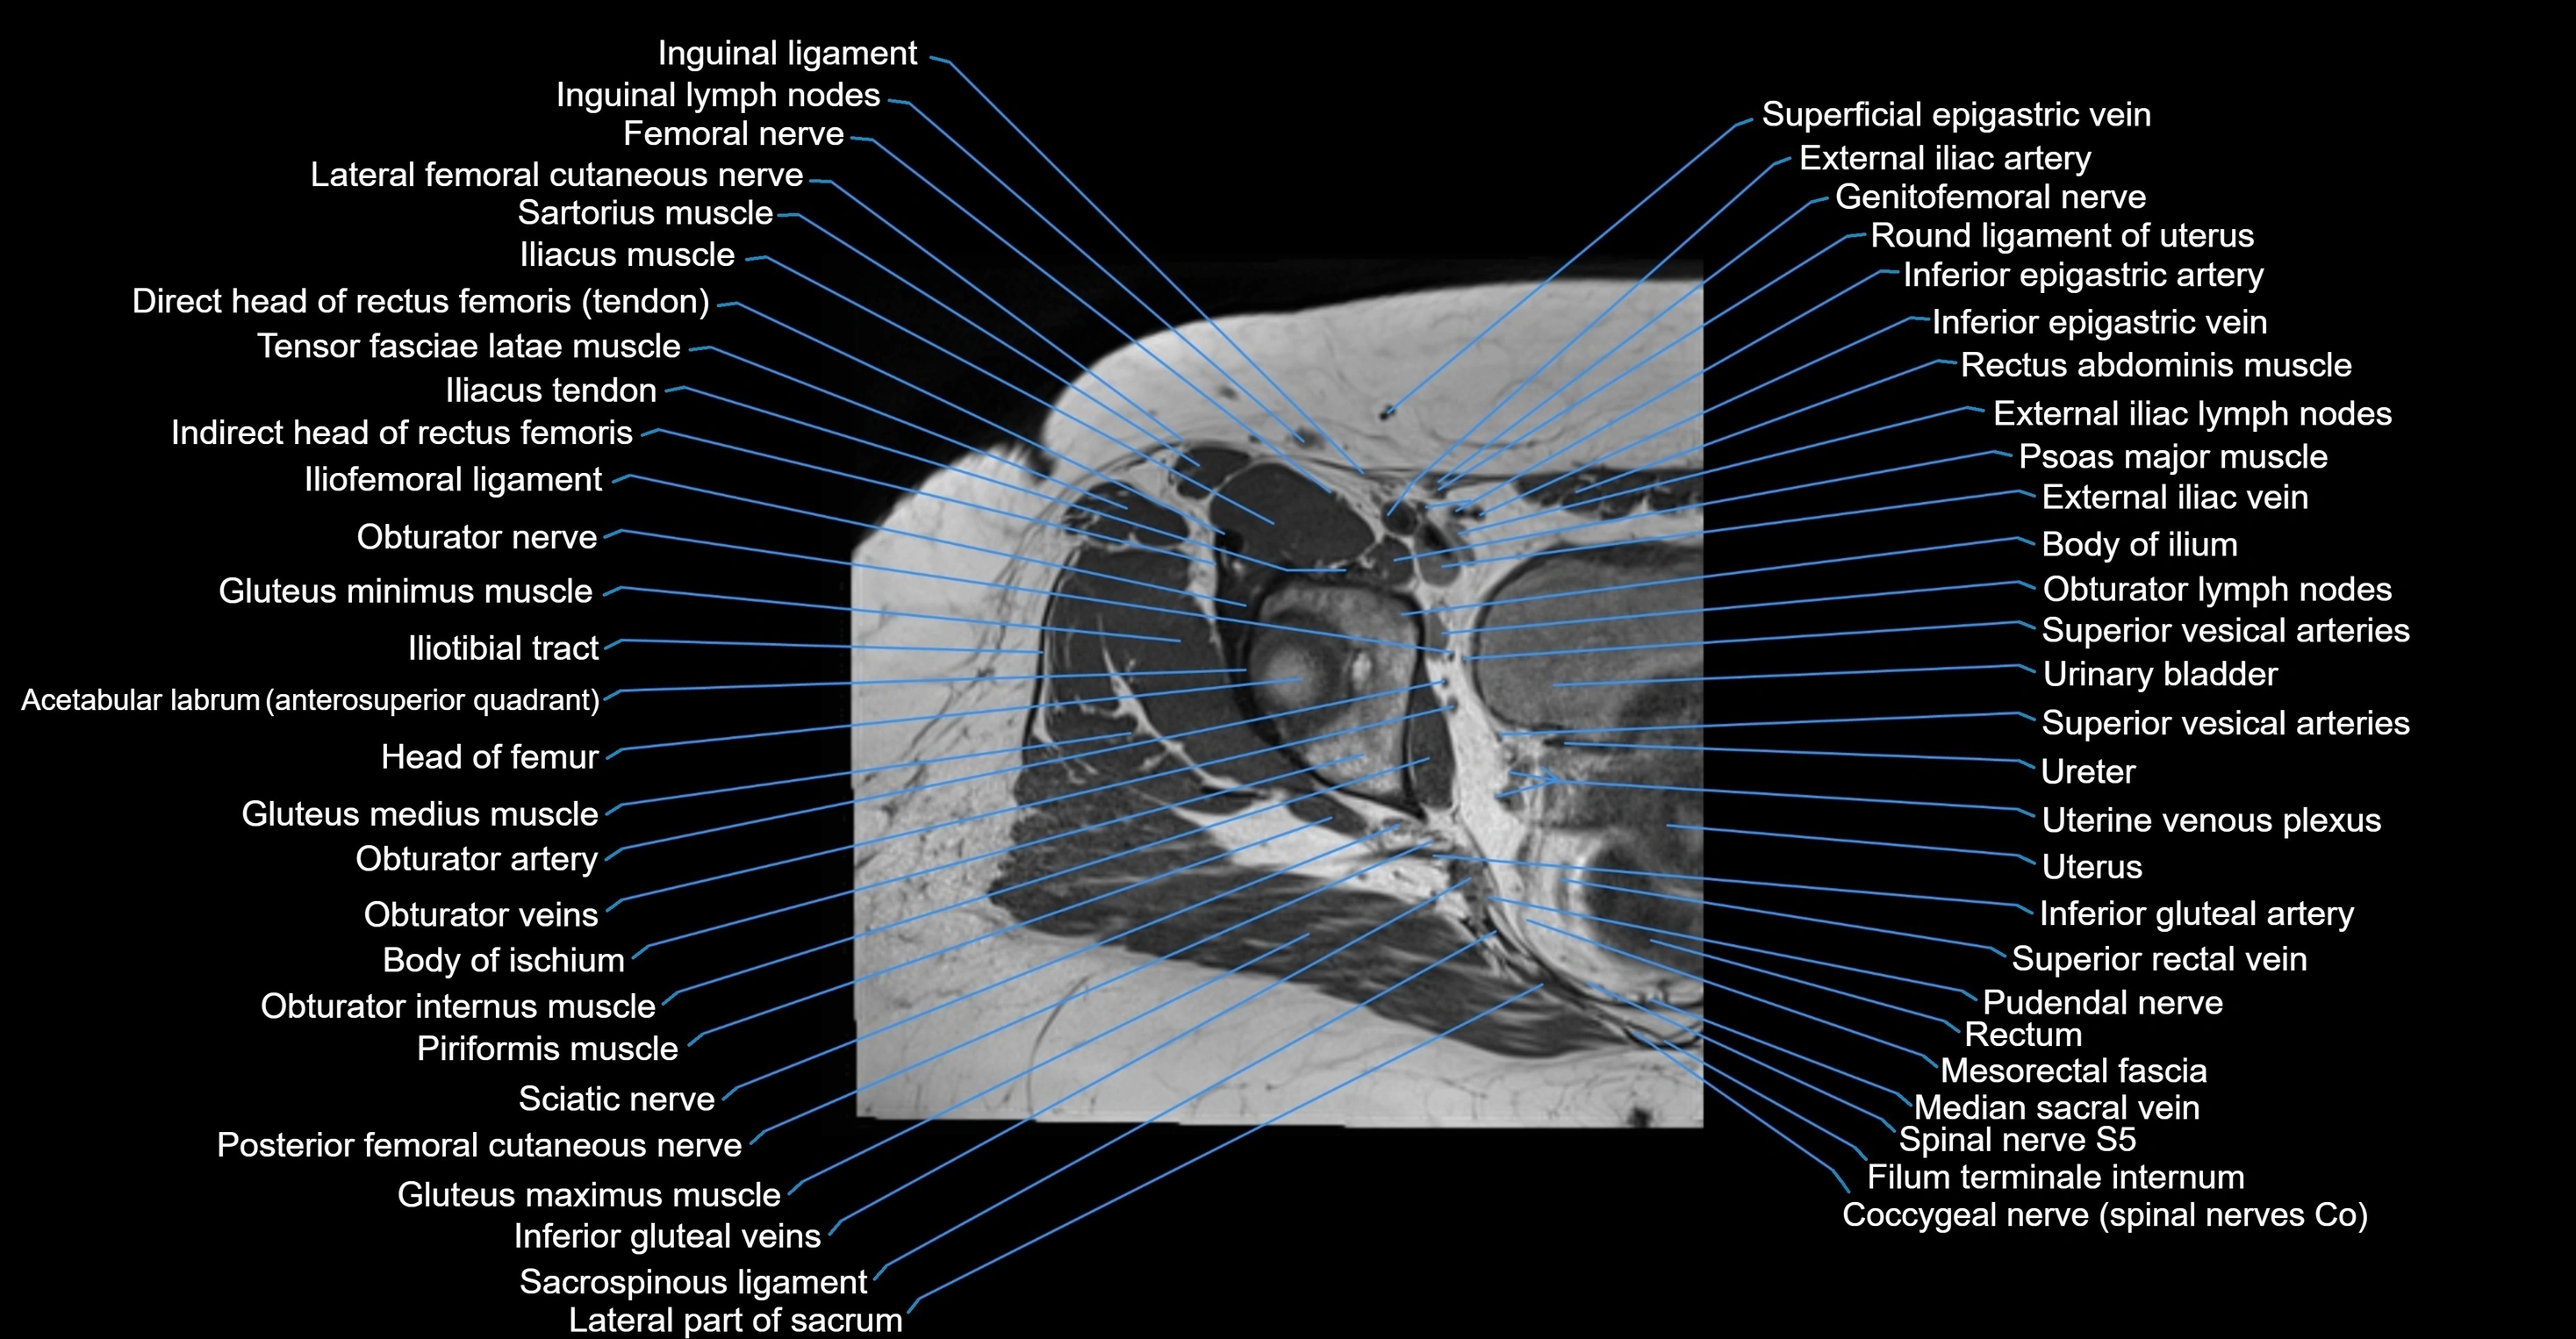

- External iliac artery

- External iliac lymph nodes

- External iliac vein

- Femoral nerve

- Genitofemoral nerve

- Head of femur

- Iliotibial tract

- Inferior epigastric artery

- Inferior epigastric veins

- Inguinal ligament

- Inguinal lymph nodes

- Lateral femoral cutaneous nerve

- Median sacral vein

- Mesorectal fascia

- Obturator artery

- Obturator internus muscle

- Obturator internus tendon

- Obturator lymph nodes

- Obturator nerve

- Obturator veins

- Posterior femoral cutaneous nerve

- Psoas major muscle

- Pudendal nerve

- Rectum

- Round ligament of uterus

- Superior rectal vein

- Superior vesical artery

- Tensor fasciae latae muscle

- Urinary bladder

- Uterine venous plexus

- Uterus